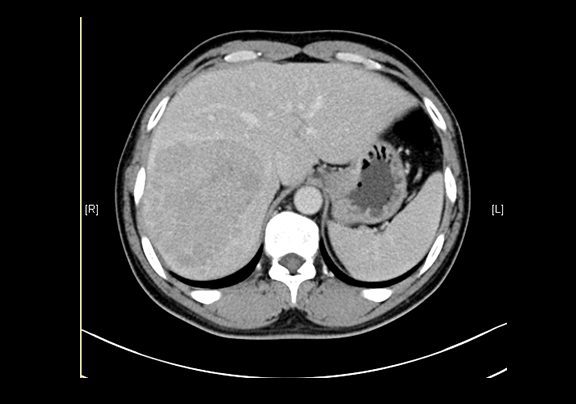

现病史:患者20余天前查体,行腹部超声检查时发现:肝右叶低回声结节,大小约5.8*4.7cm,无腹痛、腹胀,无腰背部放散痛、皮肤巩膜无黄染,无寒战、高热,无咳嗽、咳痰、胸闷、气短,无恶心、呕吐,无腹泻、血便,无尿频、尿急、尿痛、血尿。上腹部动态三维成像(增强)CT检查示,肝右后叶上段占位性病变,肿瘤性病变。

下腹部增强CT示:肝右后叶上段占位性病变,肿瘤性病变,考虑肝癌合并出血可能性大,肝多发小囊肿

术前CT检查:

动脉期

静脉期

平衡期